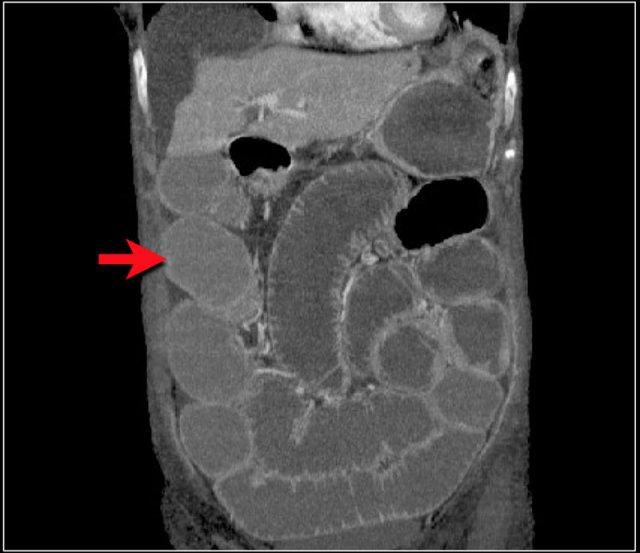

Một bệnh nhân khác với hình ảnh ruột thiếu máu cục bộ và phù nề mạc treo ruột lan rộng.

Trong phẫu thuật, toàn bộ đoạn ruột non này đã bị hoại tử.